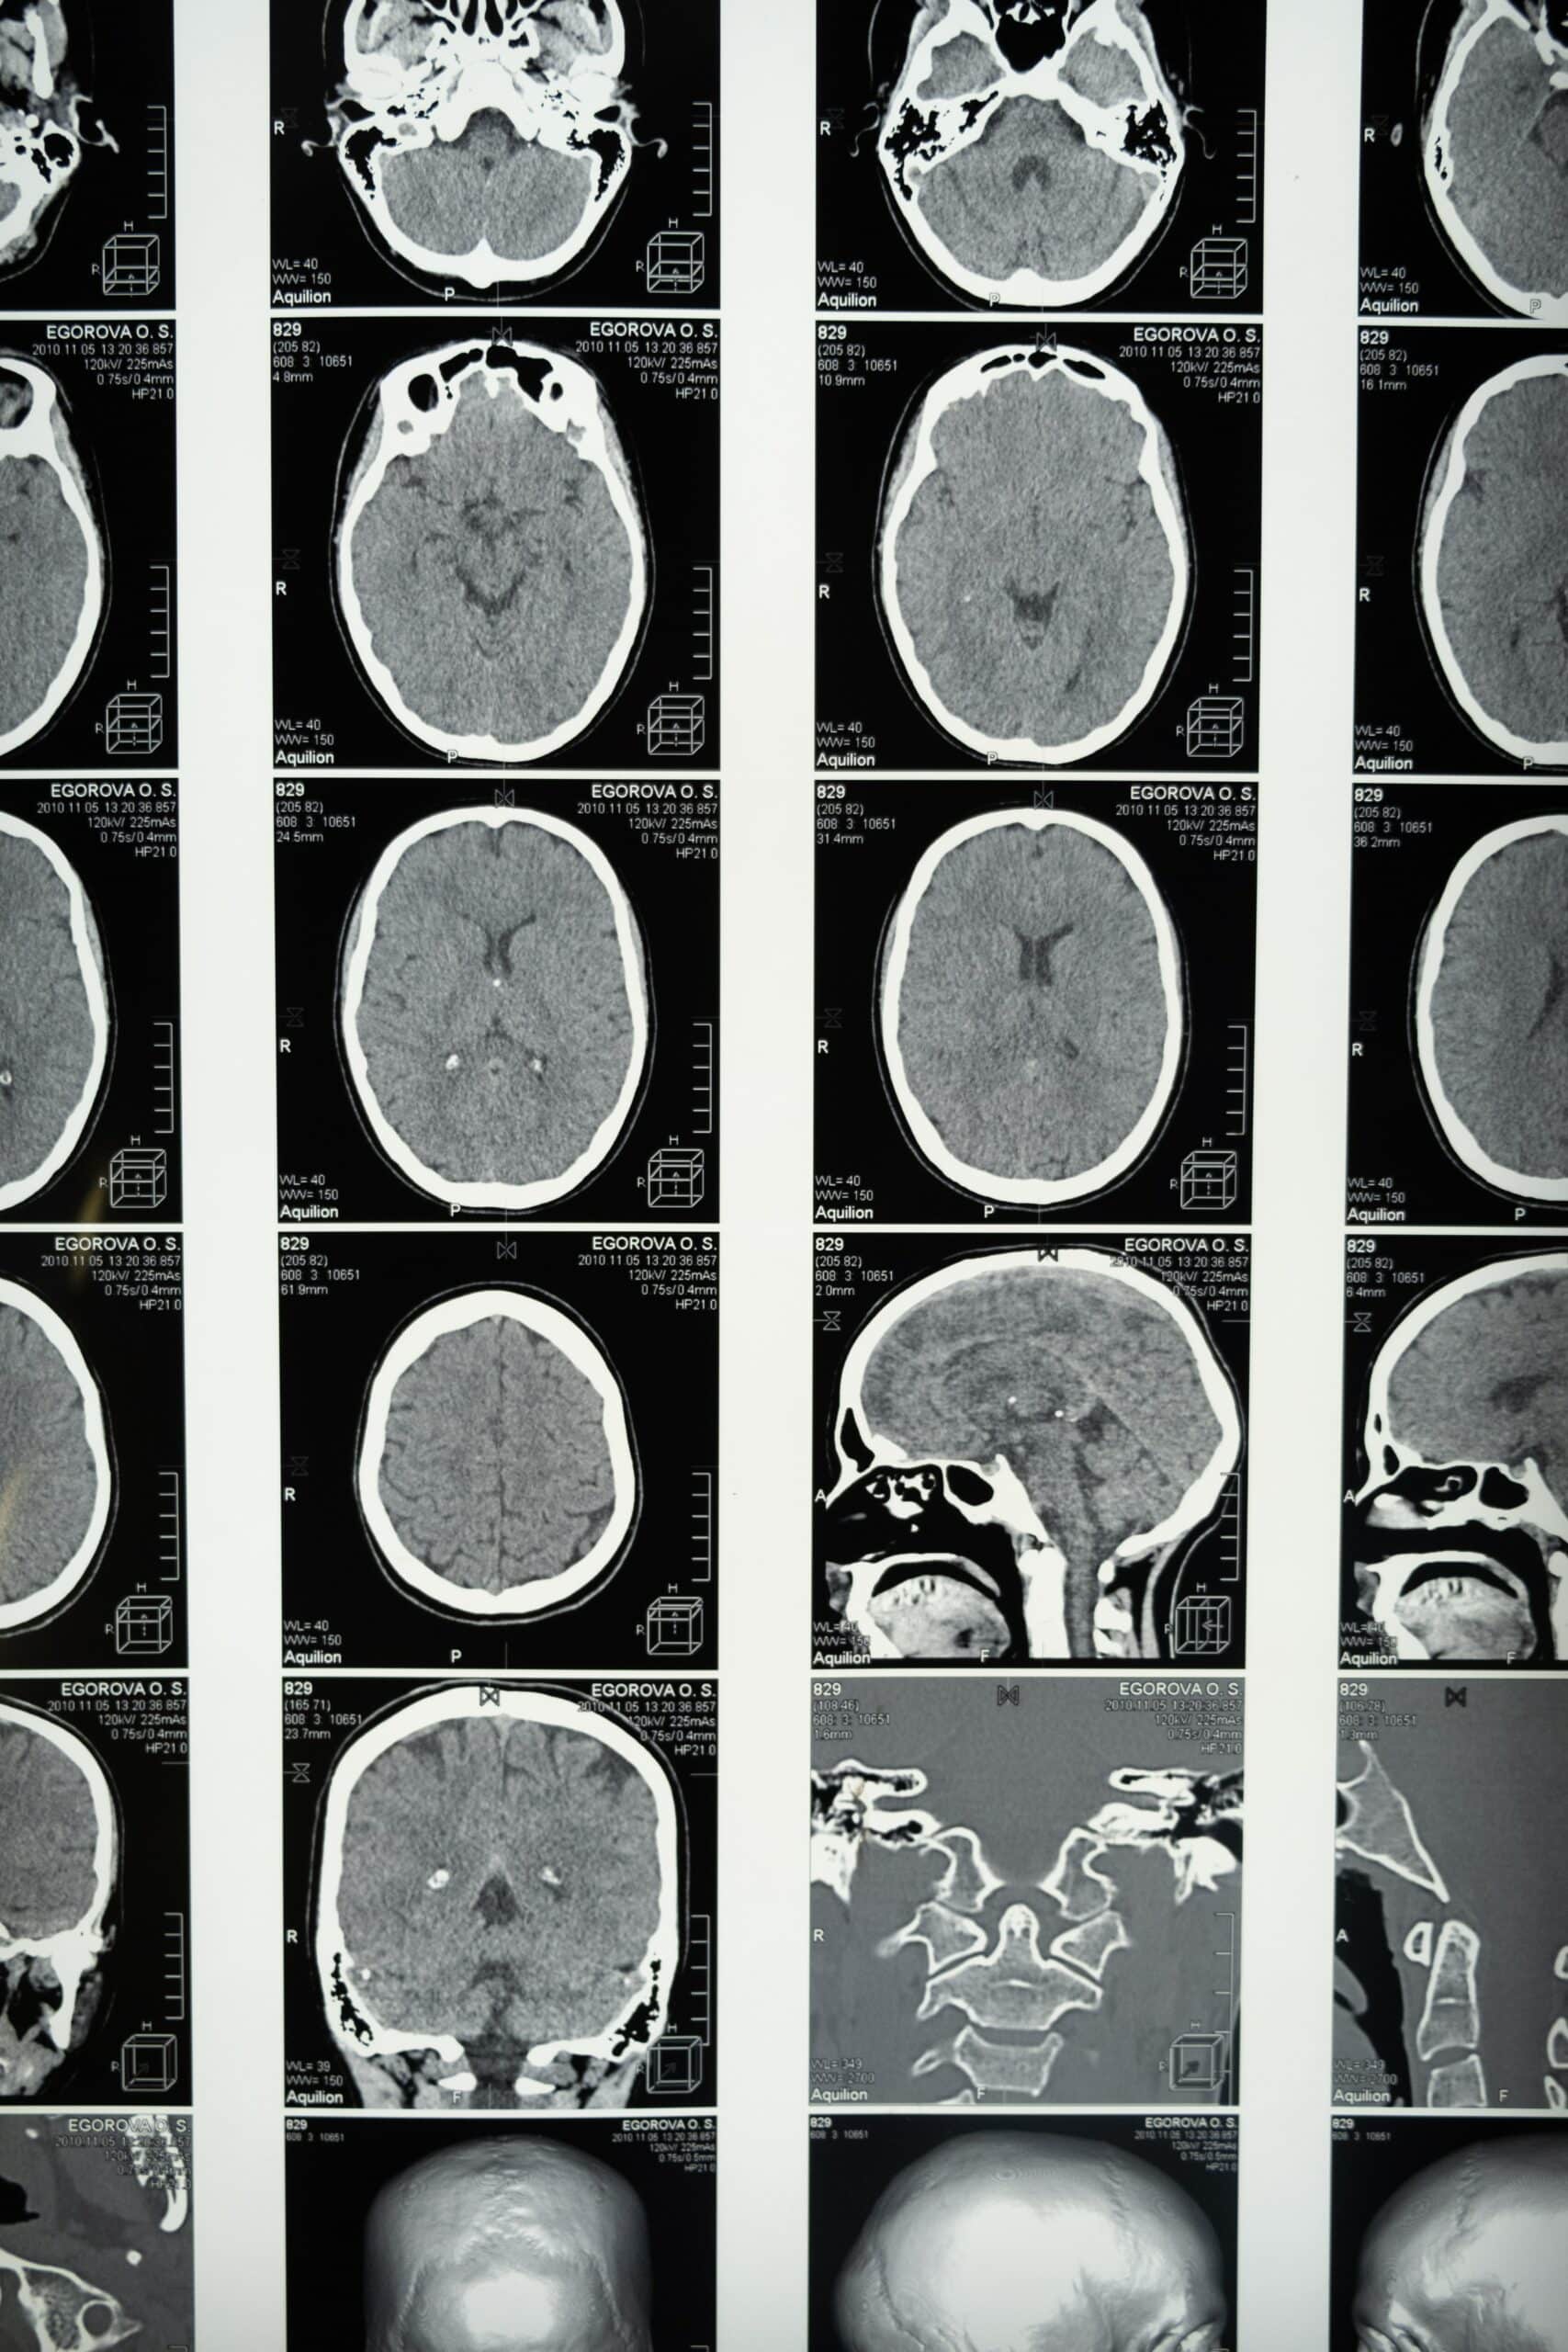

The body’s response to pornography is driven by the most complicated organ in the human body…the brain. God made our bodies with a good and beautiful design. One created facet of our bodies is that when a person experiences something enjoyable, something that the brain wants to remember and repeat, it releases dopamine.

The brain has built-in defense mechanisms within its wiring. The prefrontal cortex (PFC) is the location within the brain that helps us manage impulse control and moral reasoning. We might call these brain brakes as this is the part of the brain that helps people say no to cravings based upon their morals or goals.

Through brain scans, scientists have discovered that the PFC appears to shrink through regular use of porn, thereby offering us less ability within our brains to resist the very things we want to avoid.